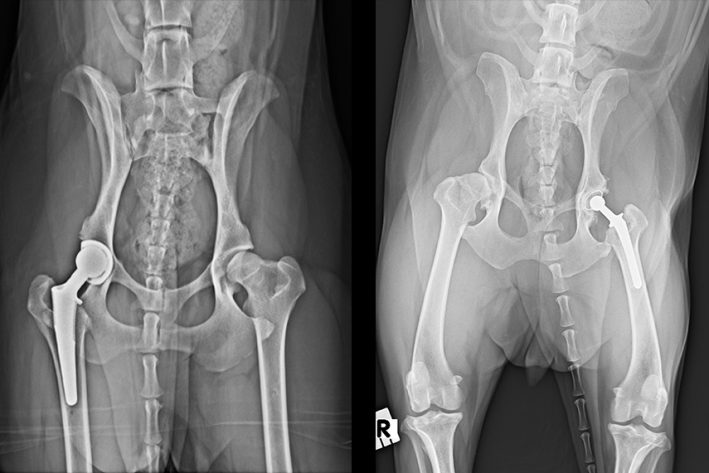

Links: Künstliches Hüftgelenk bei einem Hund, biologische Fixation. Rechts: Zementiertes künstliches Hüftgelenk bei einem kleinen Hund

2. Künstliche Hüfte

Ein künstliches Hüftgelenk stellt den gesunden, physiologischen Zustand der Hüfte wieder her und ist – wie in der Humanmedizin- OP- Methode der Wahl. Es wird eine neue Hüftpfanne sowie ein Stamm im Oberschenkelknochen mit einem neuen Kopf eingesetzt. Die Implantate bestehen aus Titan, Cobalt-Chrome und einem Ultrahigh Molecular Weight Polyethylen Liner innerhalb der Hüftpfanne. Es wird zwischen zementfixierten und biologisch fixierten Implantaten unterschieden. Traditionell wurden Pfanne und Stamm einzementiert. Heutzutage ist dies nur noch bei kleinen Hunden und Katzen nötig. Bei großen Hunden werden die Implantate in der Regel biologisch fixiert, d.h. sie werden „press-fit“ eingeschlagen. Dies hat eine bessere Verträglichkeit und eine geringere Infektionsrate zur Folge.